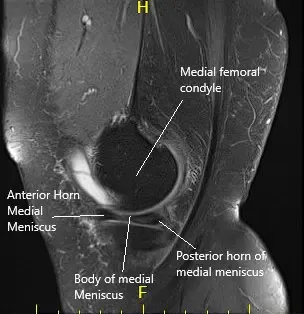

La resonancia magnética de la rodilla izquierda sugirió un desgarro complejo del cuerpo y del cuerno posterior, el menisco medial. La condromalacia patelofemoral moderada asoció derrame articular de tamaño moderado e inflamación capsular.

Resonancia magnética de la rodilla izquierda en secciones sagital y coronal.